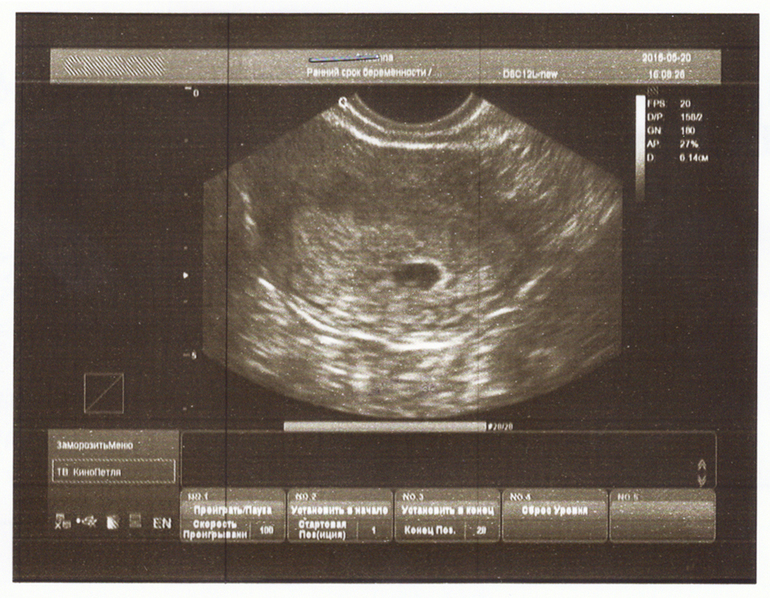

Талька 10 лет Снимок узи Моя долгожданная беременность. Не получилось Пусть растет)) 6+1 Посмотрите еще 20 записей на эту тему Отменить Ответить Alexandra вот он ваш замечательный малыш 23.08.2015 Ответить Талька главное чтобы рос)) 23.08.2015 Ответить Аnanaska Краситищаааа ))) ТТТ Растите большими и здоровыми 22.08.2015 Ответить Талька Спасибо Насть))) 22.08.2015 Ответить 6+2 7 недель Чаты Беременных Выберите чат: Январята-2026 Февралята-2026 Мартята-2026 Апрелята-2026 Майчата-2026 Июнята-2026 Июлята-2026 Августята-2026